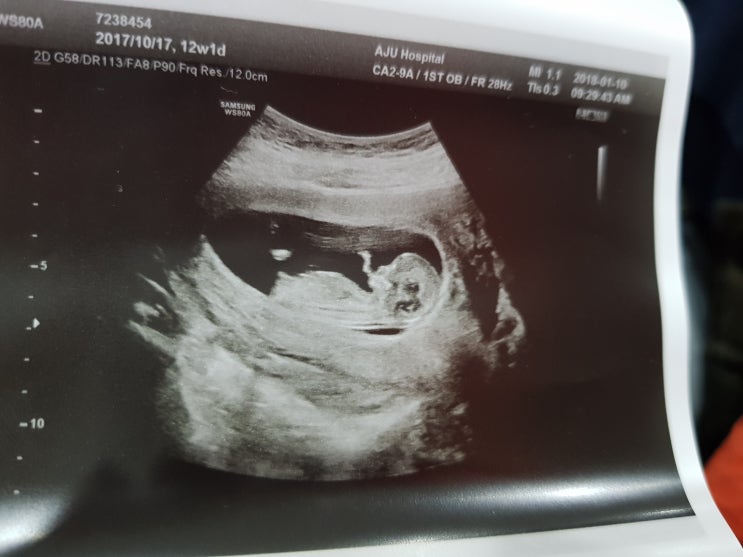

33번째 생일 최고의 선물

33번째 생일 최고의 선물 기록 : 2018. 1. 10 2018. 1. 10 만복 12주 1일3주만에 폭풍성장한 우리 만복이 ...